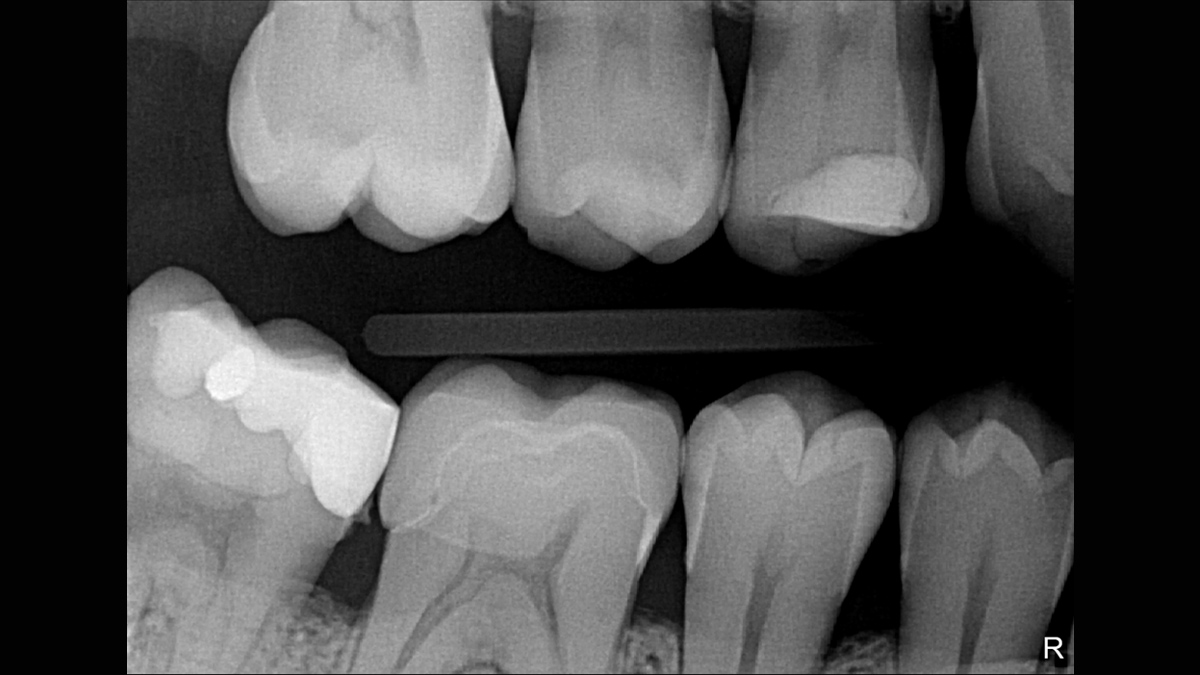

Working with Schick 33: Filtering enhancements

With Schick 33 sensors you have the option of five different filtering options: General Dentistry, Endodontics, Periodontics, Restorative and Hygiene. These clinically specific views are designed to optimize your diagnosis, enhancing the image to suit your needs.

Schick 33 - Gallery of Sample Images